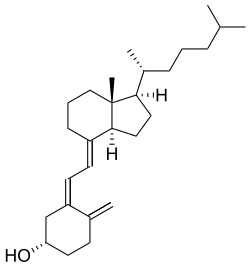

Sufficient vitamin D levels can also be achieved through dietary supplementation and/or exposure to sunlight. Vitamin D3 (cholecalciferol) is the preferred form since it is more readily absorbed than vitamin D2. Most dermatologists recommend vitamin D supplementation as an alternative to unprotected ultraviolet exposure due to the increased risk of skin cancer associated with sun exposure. Endogenous production with full-body exposure to sunlight is approximately 250 μg (10,000 IU) per day.[59]